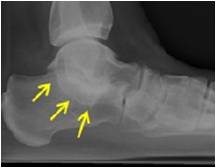

放射学检查:拍摄足负重正侧位 ,45°内斜位,跟骨轴位X线片。

放射学特征:跟距联合在侧位X线片上呈现C sign,跟舟联合在侧位X线片上呈现食蚁兽鼻征 拍摄45°内斜位X片观察跟舟联合。跟骨轴位(Harris and beath): 跟骨轴位X线片观察跟距联合。